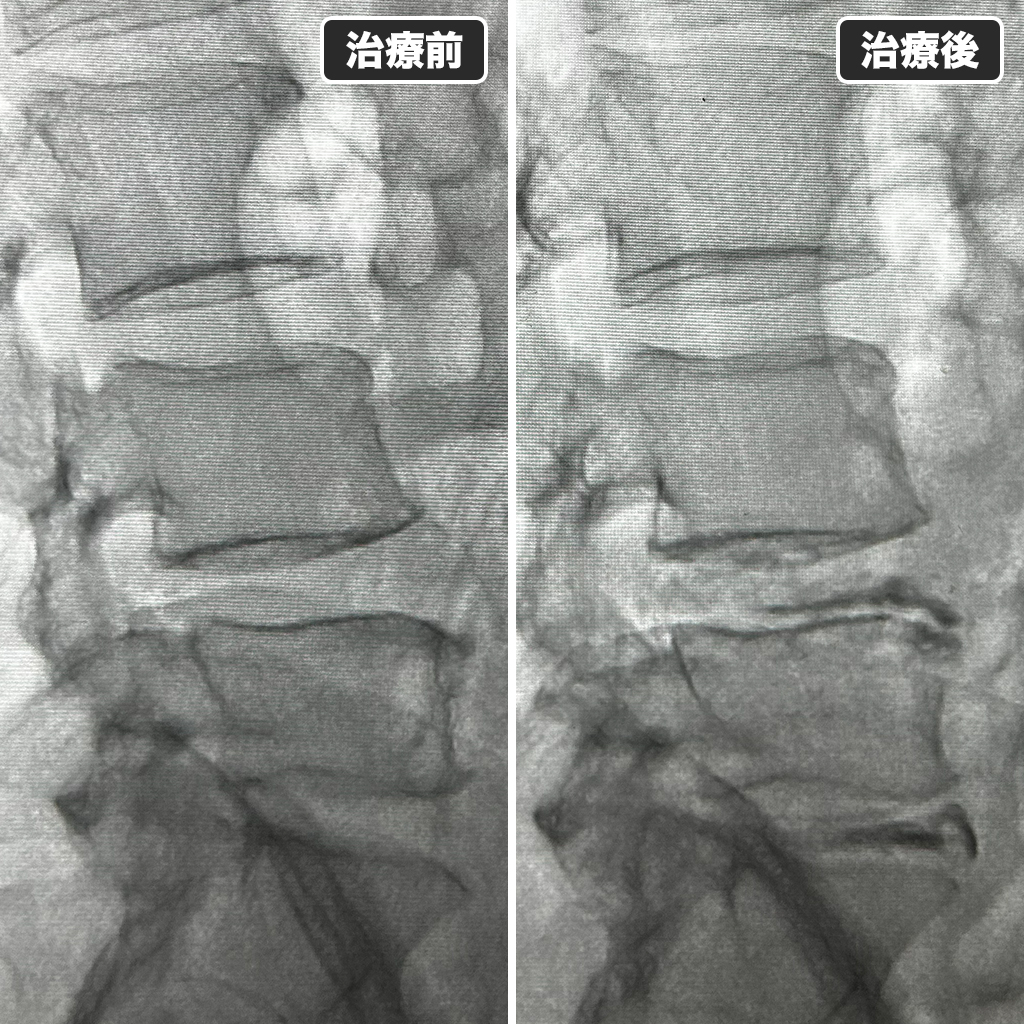

治療前後のレントゲン

治療後の画像です。一時的な椎間板容量の増大とヘルニアの形状に造影される部分を認めており、満足のいく修復が出来ました!